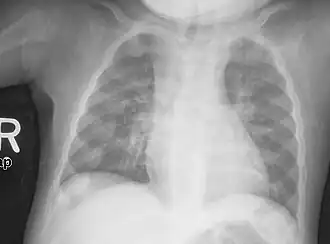

Rachitic rosary on chest radiograph

Rachitic rosary may be felt during palpitation on a physical exam, or can be seen on a chest X-ray.[8] In severe cases including malnutrition, the bony protrusions may be seen through the skin.[9]